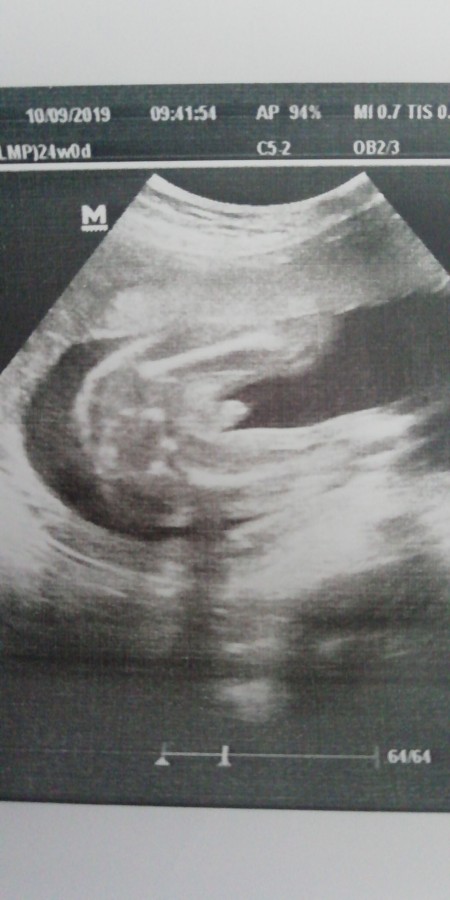

Benim ultrason resminde bacak arası bomboş arkadan çekilmiş ama hangi dr a gitsem erkek diyor varmı bunu yaşayan bilgi sahibi olan popo kısmından çekilen ultrason da pipi görünmez mi?

Gebelik haftası 17+1

Canım bebeğin bacak aradı boş. Yani erkek demeleri çok ilginç olmuş ya

Canım bacak arası net açık ama. Almış aslında görüntü. Yani hiç bir çıkıntı yokki

Canım sorgulamakta çok haklısın bende olsa aynen senin gibi sorgulardım. Ama bakınca bacak arası bomboş. Bence son bir kere daha doktora git ve tekrar erkek derse göstersin pipisini bunu söyle

Cnm ultrason ekranında gördüm zaten o yüzden acayip geldi orada gördüğüm pipi burada neden yok

Az önce bir arkadaşa danostim oda diyor ki bebegin bacak arasını arkadan alttan çekerse pipi görünür ama ayakta durmuş gibi direk çekerse görünmez de bilmiyorum 26 aralıkta ayrıntılı var ona kaldı artık kesinleşmesi hayirlisi sağlıklısı olsun

En son foto da bakar misiniz 2 bacak var ama arada birşey yok

Baktm canm cidden pipsi gozukmuorki

Bana geçen bacak arası boş bu şekilde olanları biz genelde kıza benzetiyoruz emin değilim dedi